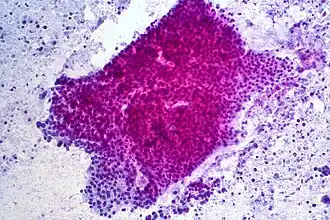

Er zijn verschillende typen alvleesklierkanker. In 85% van de gevallen gaat het om ductaal adenocarcinoom, dit is een kanker die ontstaat uit de cellen van de alvleeskliergang (ductus pancreaticus). Naast adenocarcinomen kunnen er zich ook neuro-endocriene kankersoorten ontwikkelen. Deze gaan uit van weefsels die onder meer insuline en gastrine produceren en worden overeenkomstig insulinomen en gastrinomen genoemd. Deze kankers zijn nog veel zeldzamer dan adenocarcinomen.[6]